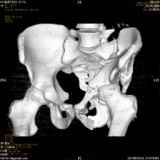

Уважаемые коллеги! Хотелось бы услышать совет по тактике лечения представлленого больного.Поступил после лечения в одном изотделений области. Травма 2,5 месяца назад. После выведенияиз шока был произведен остеосинтез перелома бедра, предплечья, до перевода к нам проводилосьвытяжение по оси шейки бедра за стержень, введенный в большой вертел. На сегодня деформацияригидна, клинически мобильности не определяется. Заранее признателен. P.S. Данный вид травм не включен в перечень "высокотехнологичных операций", направить длялечения по квотам Минздрава очень сложно.

Это обзорные и косые снимки

С уважением,

Привет, Леонид. Оскольчатый высокий двухколонный перелом в такие сроки трогать не надо, т.к. это про такие переломы сказано: "кто с ножом на Ж. пойдет тот в ней и останется...".